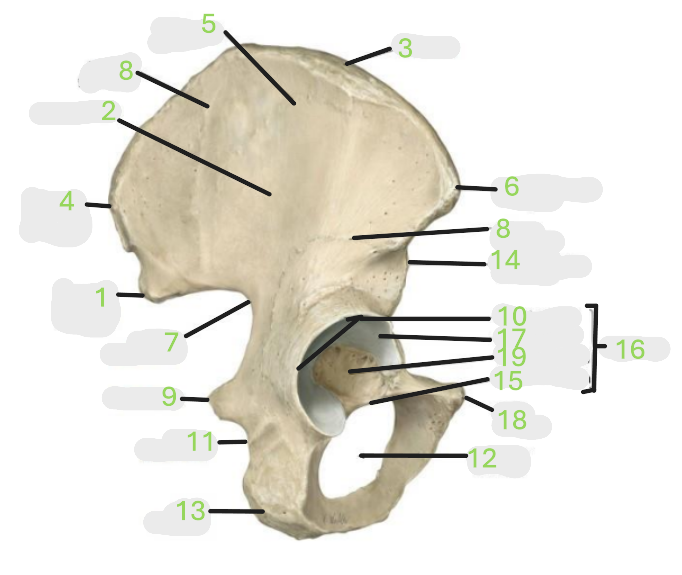

Where is the posterior inferior iliac spine

1

Where is the gluteal surface

2

Where is the iliac crest

3

Where is the posterior superior iliac spine

4

Where is the anterior gluteal line

5

Where is the anterior superior iliac spine

6

Where is the greater sciatic notch

7

Where is the inferior gluteal line

8

Where is the ischial spine

9

Where is the acetabular rim

10

Where is the lesser sciatic notch

11

Where is the obturator foramen

12

Where is the ischial tuberosity

13

Where is the anterior inferior iliac spine

14

Where is the acetabular notch

15

Where is the acetabulum

16

Where is the lunate surface

17

Where is the pubic tubercle

18

Where is the acetabular fossa

19